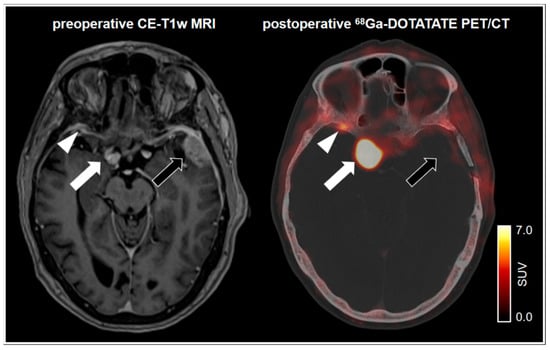

- Rachinger, W.; Stoecklein, V.M.; Terpolilli, N.A.; Haug, A.R.; Ertl, L.; Pöschl, J.; Schüller, U.; Schichor, C.; Thon, N.; Tonn, J.-C. Increased 68Ga-DOTATATE Uptake in PET Imaging Discriminates Meningioma and Tumor-Free Tissue. J. Nucl. Med. 2015, 56, 347–353. [Google Scholar] [CrossRef] [PubMed]

- Kunz, W.G.; Jungblut, L.M.; Kazmierczak, P.M.; Vettermann, F.J.; Bollenbacher, A.; Tonn, J.C.; Schichor, C.; Rominger, A.; Albert, N.L.; Bartenstein, P.; et al. Improved Detection of Transosseous Meningiomas Using 68Ga-DOTATATE PET/CT Compared with Contrast-Enhanced MRI. J. Nucl. Med. 2017, 58, 1580–1587. [Google Scholar] [CrossRef]

- Unterrainer, M.; Ruf, V.; Ilhan, H.; Vettermann, F.J.; Cyran, C.C.; Niyazi, M.; Bartenstein, P.; Tonn, J.-C.; Albert, N.L. 68Ga-DOTATOC PET/CT Differentiates Meningioma from Dural Metastases. Clin. Nucl. Med. 2019, 44, 412–413. [Google Scholar] [CrossRef] [PubMed]

- Cornelius, J.F.; Langen, K.J.; Stoffels, G.; Hänggi, D.; Sabel, M.; Steiger, H.J. Positron Emission Tomography Imaging of Meningioma in Clinical Practice. Neurosurgery 2011, 70, 1033–1042. [Google Scholar] [CrossRef]

- Nyuyki, F.; Plotkin, M.; Graf, R.; Michel, R.; Steffen, I.; Denecke, T.; Geworski, L.; Fahdt, D.; Brenner, W.; Wurm, R. Potential impact of 68Ga-DOTATOC PET/CT on stereotactic radiotherapy planning of meningiomas. Eur. J. Nucl. Med. Mol. Imaging 2009, 37, 310–318. [Google Scholar] [CrossRef] [PubMed]

- Graf, R.; Nyuyki, F.; Steffen, I.G.; Michel, R.; Fahdt, D.; Wust, P.; Brenner, W.; Budach, V.; Wurm, R.; Plotkin, M. Contribution of 68Ga-DOTATOC PET/CT to Target Volume Delineation of Skull Base Meningiomas Treated with Stereotactic Radiation Therapy. Int. J. Radiat. Oncol. 2013, 85, 68–73. [Google Scholar] [CrossRef] [PubMed]

- Milker-Zabel, S.; Bois, A.Z.-D.; Henze, M.; Huber, P.; Schulz-Ertner, D.; Hoess, A.; Haberkorn, U.; Debus, J. Improved target volume definition for fractionated stereotactic radiotherapy in patients with intracranial meningiomas by correlation of CT, MRI, and [68Ga]-DOTATOC-PET. Int. J. Radiat. Oncol. 2006, 65, 222–227. [Google Scholar] [CrossRef]